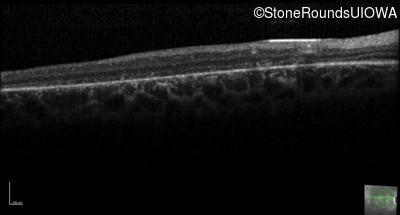

AR Stargardt Disease (IIA)

AR Stargardt Disease (IIA)

| Age at visit: 12 years |

| Age at visit: 13 years |

| Age at visit: 15 years |